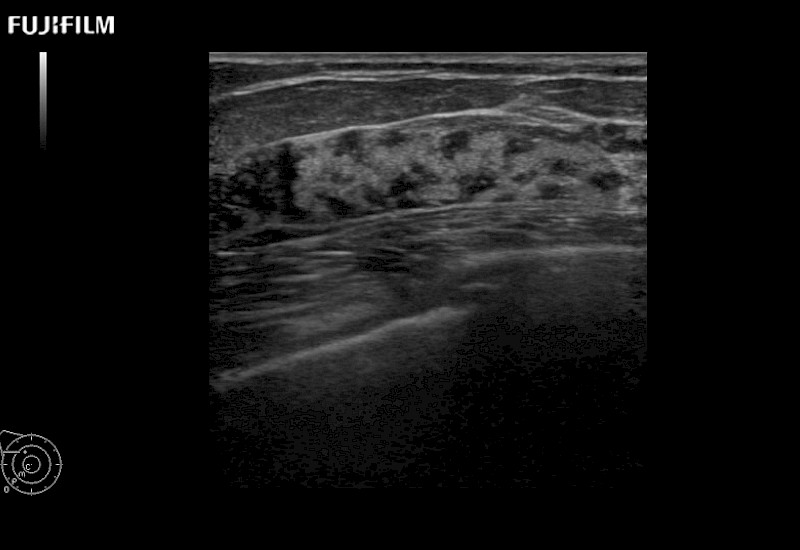

Learn moreFujifilm Healthcare continues to listen to the experts, our neurosurgeons, by developing an ultrasound system specifically designed for the Operating Room.

Guidance is the fundamental purpose for all of our surgical ultrasound technology. Fujifilm Healthcare is committed to designing tools that help neurosurgeons navigate inside the human body and provide the necessary information to immediately make critical surgical decisions.

With the ARIETTA Precision the next level of surgical ultrasound is here.